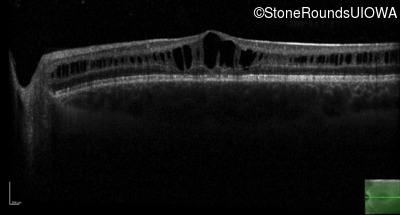

Age at visit: 11 years

This 11 year old male was never correctable to 20/20. He received glasses at age 1 for esotropia. His refraction is +4.25 +2.00 x 105 OD and +2.00 +2.00 x 80 OS.

Age at visit: 13 years

Age at visit: 15 years

Age at visit: 17 years

Age at visit: 18 years